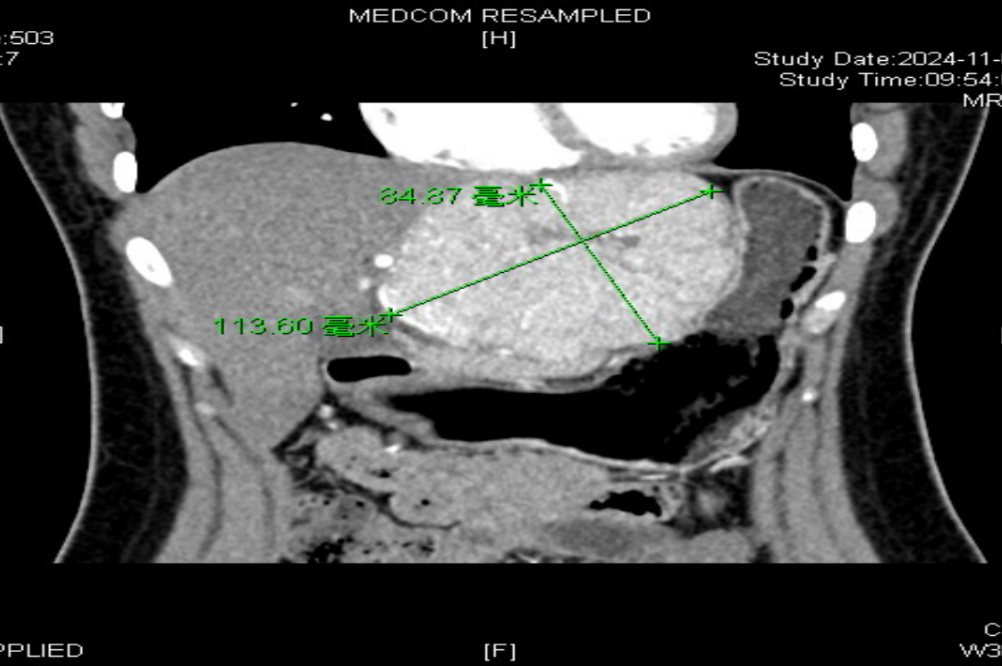

体检后发现左肝

居然长出了一个“大疙瘩”

直径约11cm

进一步检查后

确诊为肝局灶性结节性增生